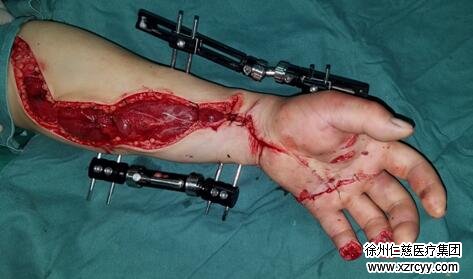

10天后,王云龙病情趋于平稳,从ICU挪出,手术团队为他进行了第二次手术,对左股骨干骨折予以外固定架固定,左小腿残端修复。术后,他被安排入住手外三病区,继续用药康复。